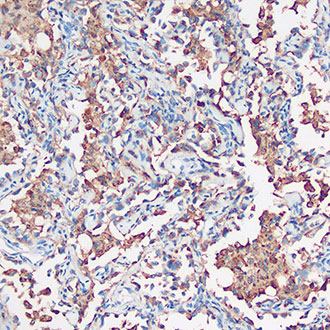

IHC

免疫组织化学(IHC)